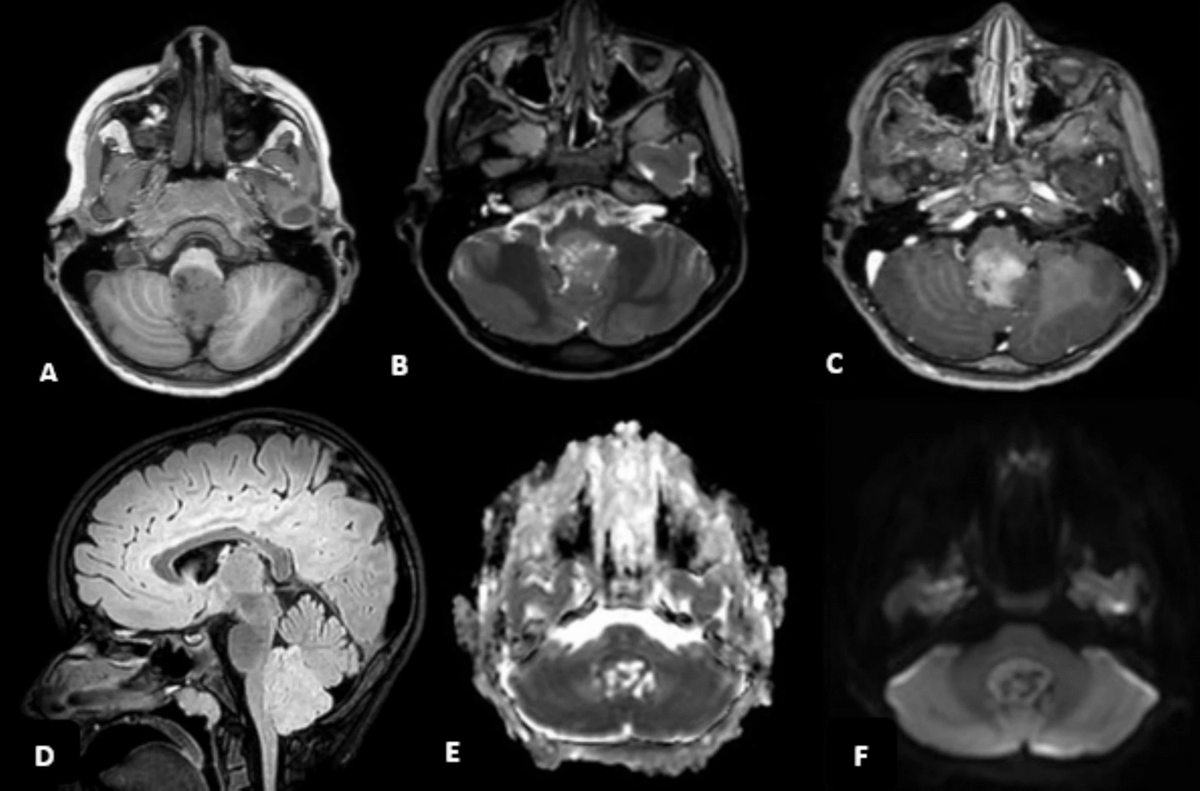

@DocNavarrow Habría dicho meduloblastoma hasta demostrar lo contrario. Los astroblastomas ya son muy raros y más en la fosa posterior.

<What's your diagnosis?>

20 yo Male w/ recurrent neuro sx x12y:

Initial episode @ 8 yo → dx'd viral encephalitis

Recent: 5d GTC sz

Sx include: GTC sz, choreoathetosis, dystonia, hypotonia, apraxia, ataxia

All negative: LP, infectious/rheum w/u, mito panel, muscle bx

#Rdiag